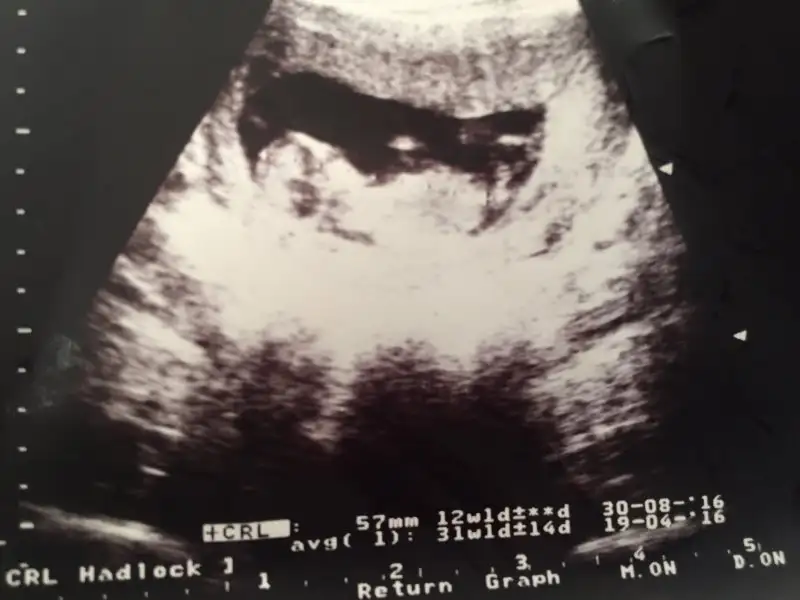

Resimdeki sacaklida benim ehuehu

image.webp

Bebek 5.7 mm olmuş. Kalbi atıyor dedi ben daha üzerimi toplamadan diğer hastayı aldı içeri seri üretim gibi.